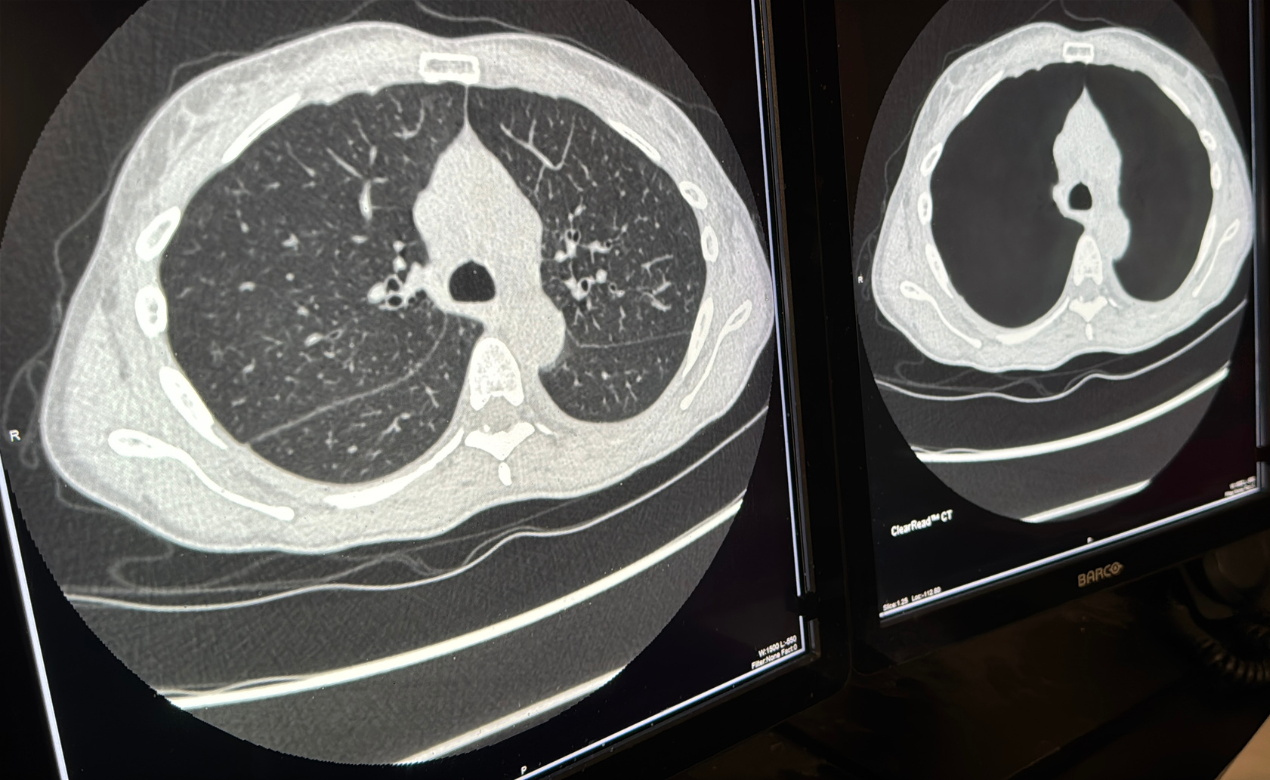

The AI tools she’s implemented, such as the ClearRead system, have transformed how she approaches lung cancer screening. These advanced programs don’t just make the process more efficient; they improve accuracy and help radiologists spot what could otherwise be missed. “We are the first institution in the region using this technology to read more exams and to be able to find more of these nodules and help our patients.”

The ClearRead technology narrows down potential problematic nodules by clearing up all normal structures except the nodule from the image, thus removing "visual clutter" and allowing a radiologist like Dr. Kapur to go from focusing on dozens of spots to a handful of spots that truly need attention. The AI software can review scans in a matter of minutes. Despite this, Dr. Kapur calls the AI tool her “second reader” with staff always having the final look.

ClearRead’s unique vessel suppression capability allows radiologists to focus on the areas that matter most, enhancing the conspicuity of lung nodules.

“The first day the technology came into our department, I was sold because I had seen it in action, but my colleagues were just floored,” Dr. Kapur recalled when the AI software launched as the new standard for lung cancer screening at the University of Cincinnati Cancer Center in February 2024. “They were like, ‘This thing is unbelievable.’ How it finds all the nodules every time it measures them, it shows you what they are and what consistency they are, and then puts them in the report. I couldn't have asked for something better.”

The inner workings of ClearRead are impressive, rooted in cutting-edge machine learning and deep training with thousands of varied nodule cases. This has made it adaptable, even across different CT scan machines and settings. This adaptability is crucial for cancer centers like the University of Cincinnati Cancer Center that handle a broad range of cases and technologies.

What sets ClearRead apart is its precision in detecting nodules as small as 5 mm. In the past, these small findings could be easily overloofked, buried under a labyrinth of vessels and other normal structures. ClearRead minmizes these obstacles, and every nodule, whether solid, part-solid, or ground-glass, is assessed with improved clarity. This technology even provides automatic measurements for detected nodules, including their type, volume, and dimensions, supporting more accurate assessments.